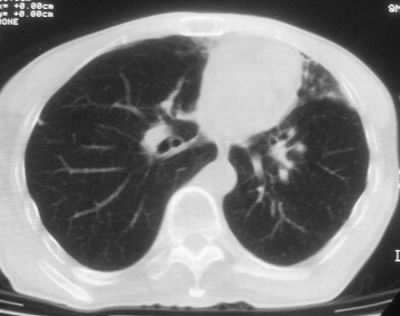

标题: CT11864:男,47岁,反复咳嗽、咯痰、咯血3年,请分析. [打印本页]

患者,男,47岁,反复咳嗽、咯痰、咯血3年,再发5天。痰培养未找到真菌、抗酸杆菌、癌细胞。

左肺上叶体积明显缩小,其内见多发透光区,纵隔向左侧移位,左肺下叶多发班片状病灶,边界模糊,1左肺上叶先天肺发育不全,2左肺下叶肺炎,

左肺上叶结核伴肺纤维化,纵隔移位,左肺下叶感染性病变,建议抗炎抗结核后复查,双肺气肿.

1)考虑为:左肺上叶肺结核(空洞形成),伴左下肺感染;不排除霉菌感染可能。2)肺气肿。

左肺上叶结核伴肺纤维化空洞形成并左肺下叶感染,纵隔牵拉移位,建议作进一步检查排除左侧肺霉菌感染可能。